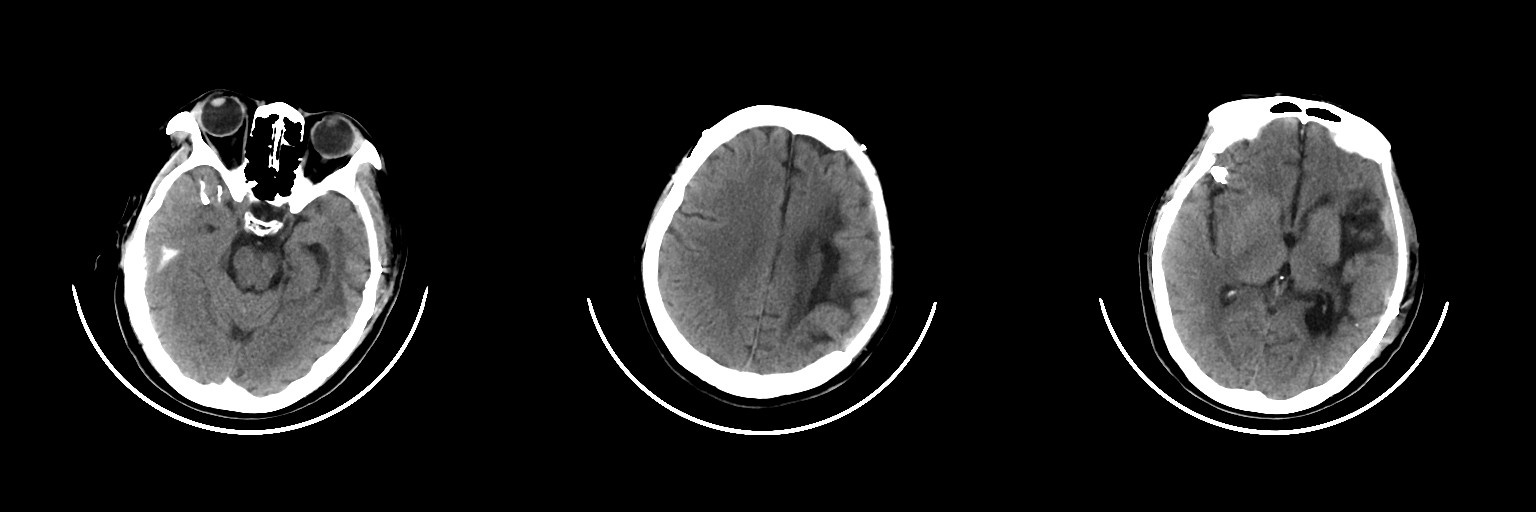

術后1天復查頭顱CT

2024年3月1日患者晨起后突發頭暈,繼而意識不清,急被送至當地醫院就診,行頭顱CT檢查,結果顯示:“左側基底節區腦出血”。急診手術治療,行開顱血腫清除、去骨瓣減壓術,術后患者逐漸清醒,遺留失語,右側肢體偏癱。后續行肢體功能鍛煉、針灸、高壓氧等康復治療。